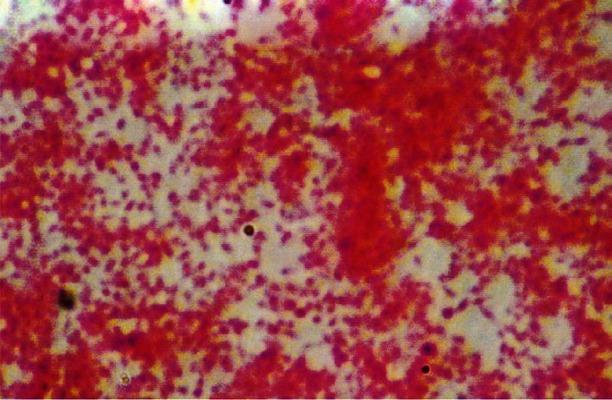

B. henselae ATCC 49882 strain was procured from American type culture collection, USA. This strain was revived and maintained in the laboratory, and identification and characterization of this strain was done by conventional and molecular techniques, which included culture on various media, staining by different methods including electron microscopy, biochemical analysis by conventional methods and API, polymerase chain reaction (PCR) for amplification of citrate synthase gene followed by restriction fragment length polymorphism (RFLP).

从美国典型培养物保藏中心(American Type Culture Collection,USA)获得巴尔通体(Bartonella)菌株 ATCC 49882。该菌株在实验室中复苏和保存,并通过常规和分子技术进行鉴定和特征描述,包括在不同培养基上的培养、不同方法的染色,包括电子显微镜、传统 API 的生化分析、扩增柠檬酸合酶基因的聚合酶链反应(PCR),随后进行限制性片段长度多态性(RFLP)分析。